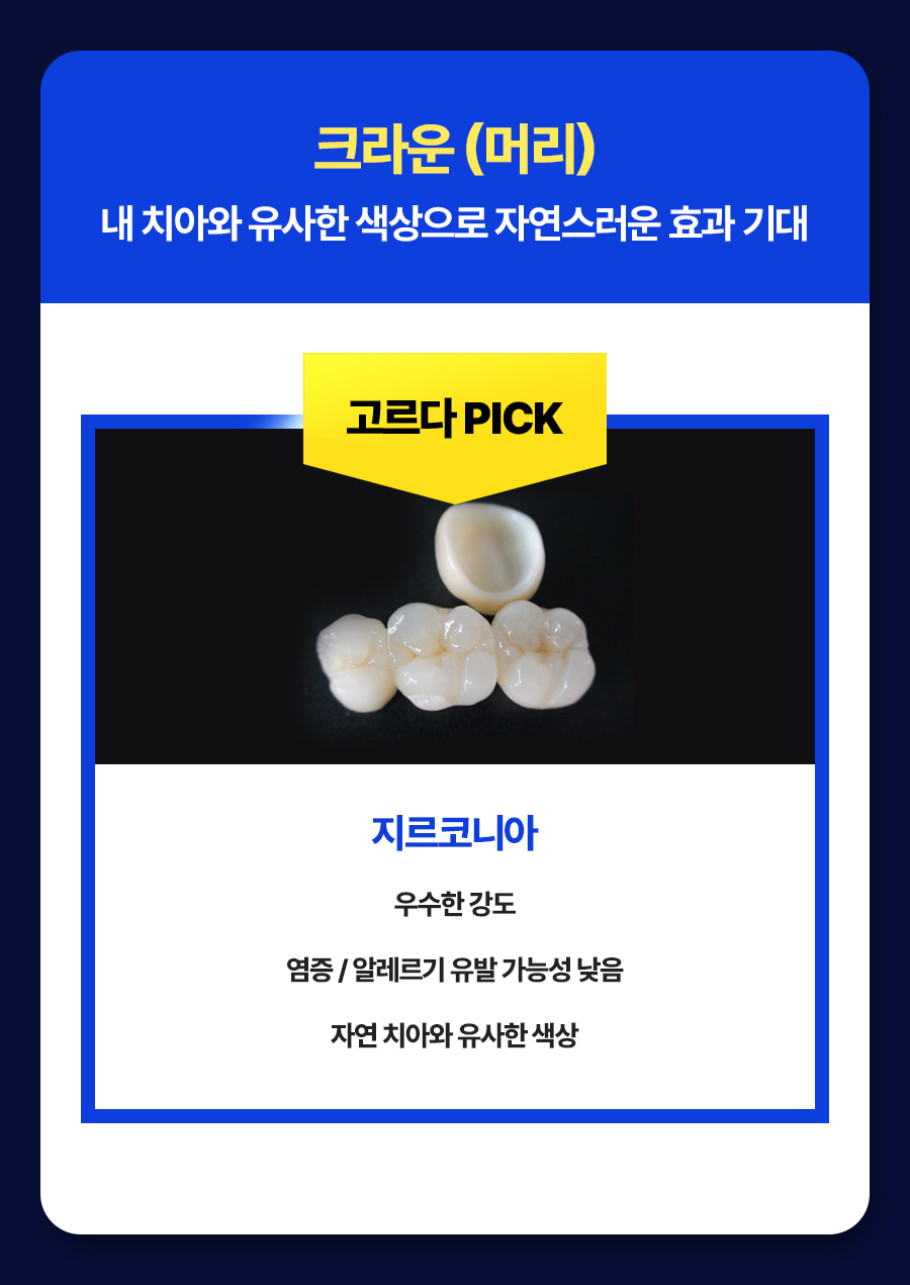

When undergoing full implant treatment, the condition of your oral cavity is the most significant factor. The density and height of the remaining jawbone affect the placement, angle, number, and structure of the implants. Generally, at least 12 implants are placed in both the upper and lower jaws. However, depending on the oral structure, the design may involve only 8 or 10 implants. Of course, reducing the number of implants doesn't necessarily lower the cost. In some cases, expensive materials are used to enhance stability. Therefore, a design tailored to each individual's condition is crucial.

The price typically starts at around 10 million won and can exceed 20 million won. This is based on the structure of a full set of dentures, and the cost can vary by more than 5 million won depending on the individual's gum condition, desired materials, and denture type. This is why dental clinics provide various options before starting treatment. The terminology and methods may seem difficult at first, but understanding them will clarify which option is best for you. The cost of Seomyeon implants can be flexibly adjusted depending on the chosen configuration.

To find the right configuration and treatment plan for you, it's necessary to listen to detailed explanations and carefully compare the required conditions. The cost of Seomyeon implants is not simply determined by a single number. It's a process of carefully adjusting the structure, materials, and condition, requiring extra caution. Even if it seems overwhelming at first, you can find a solution by gradually organizing your thoughts. A small choice can affect the overall treatment outcome, so a careful approach is needed.